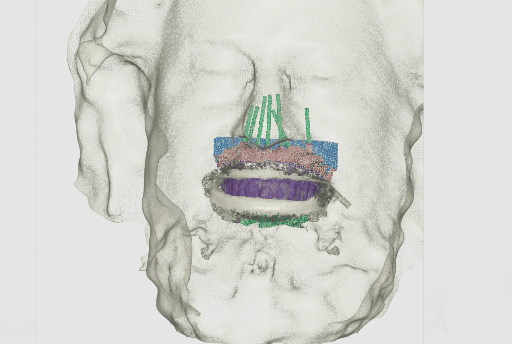

Digital patient with integrated facial scan, intraoral scan of the maxillas, and with dentures.

1.5 Merging the CBCT to the Facial and Intraoral Scans

In order to integrate the CBCT to the data captured from the intraoral and extraoral scan, a CBCT was done on the patient while wearing the dentures with added anatomical landmarks. The integration of the data with the CBCT will allow the implant planning and consecutive steps.

CBCT of the patient and anatomical landmarks on the denture captured (RealGuide).

Aligning relined denture plus intraoral data to the anatomical landmarks in the CBCT.

Intraoral data (soft tissue) aligned to the CBCT.

Aligning CBCT with the dentures with anatomical landmarks.